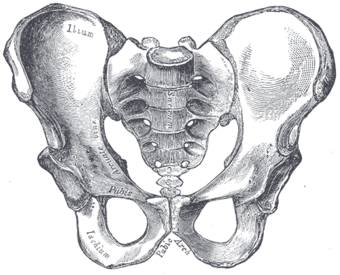

Male type pelvis | |

Female type pelvis | |

The principal differences between male and female true and false pelvis include:

- The female pelvis is larger and broader than the male pelvis which is taller, narrower, and more compact.[9] The female pelvis is lighter and thinner than the male pelvis.[10]

- The female inlet is larger and oval in shape, while the male sacral promontory projects further (i.e. the male inlet is more heart-shaped).[9]

- The sides of the male pelvis converge from the inlet to the outlet, whereas the sides of the female pelvis are wider apart.[11]

- The angle between the inferior pubic rami is acute (70 degrees) in men, but obtuse (90–100 degrees) in women. Accordingly, the angle is called subpubic angle in men and pubic arch in women.[9] Additionally, the bones forming the angle/arch are more concave in females but straight in males.[12]

- The distance between the ischia bones is small in males, making the outlet narrow, but large in females, who have a relatively large outlet. The ischial spines and tuberosities are heavier and project farther into the pelvic cavity in males. The greater sciatic notch is wider in females.[12]

- The iliac crests are higher and more pronounced in males, making the male false pelvis deeper and more narrow than in females.[12]

- The male sacrum is long, narrow, more straight, and has a pronounced sacral promontory. The female sacrum is shorter, wider, more curved posteriorly, and has a less pronounced promontory.[12]

- The acetabula are wider apart in females than in males.[12] In males, the acetabulum faces more laterally, while it faces more anteriorly in females. Consequently, when males walk the leg can move forwards and backwards in a single plane. In females, the leg must swing forward and inward, from where the pivoting head of the femur moves the leg back in another plane. This change in the angle of the femoral head gives the female gait its characteristic (i.e. swinging of hips).[13]